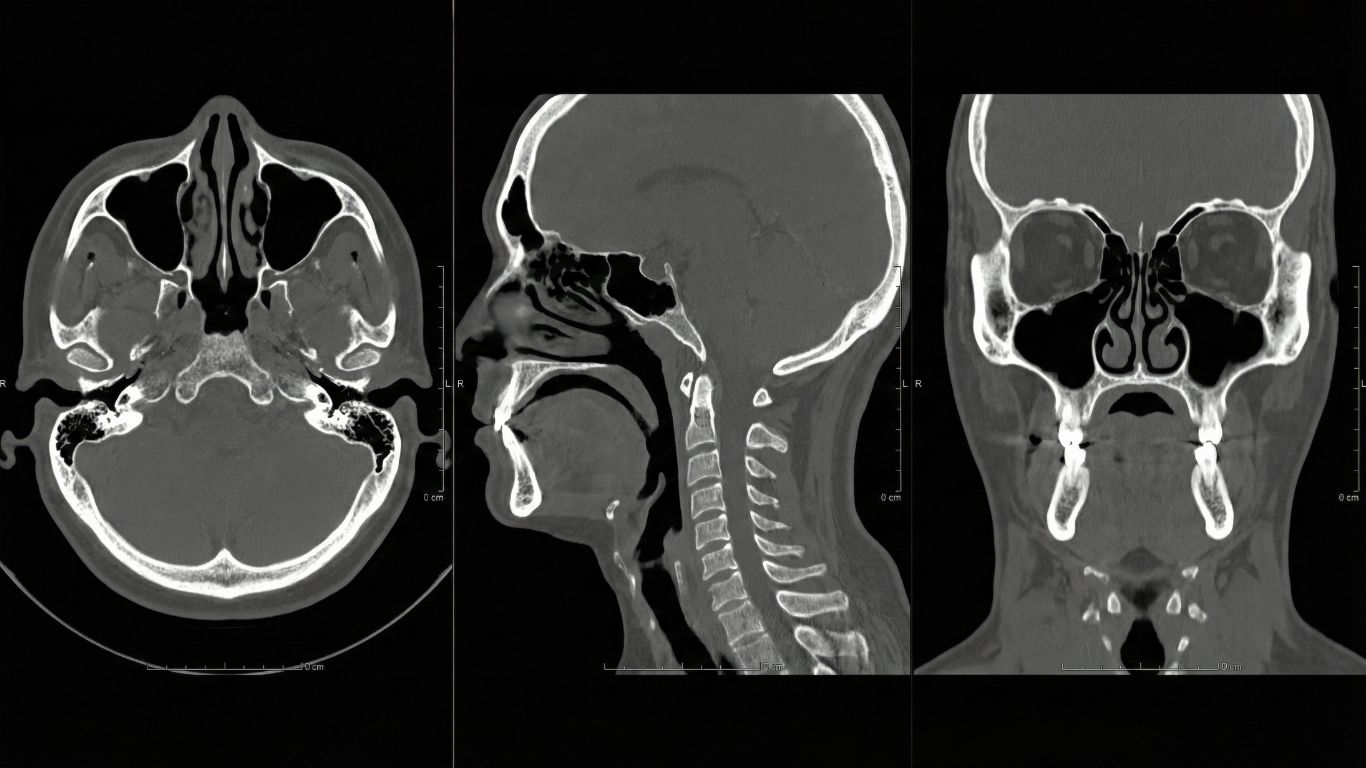

En el ámbito de los diagnósticos médicos, la tomografía se destaca como una herramienta fundamental. Pero, ¿qué es la tomografía? Este procedimiento utiliza radiografías para crear imágenes transversales de alta resolución de las estructuras internas del cuerpo. La importancia de la tomografía radica en su capacidad para ofrecer detalles que otras técnicas diagnósticas no logran captar, mejorando así la precisión en la detección de enfermedades.

Gracias a la tomografía, los médicos pueden observar órganos, tejidos y posibles patologías, facilitando diagnósticos más tempranos y eficaces. Este avance tecnológico se convierte en un aliado esencial en el proceso de identificación de condiciones de salud y en la planificación de tratamientos adecuados.

La tomografía simple se utiliza para obtener imágenes nítidas de las estructuras internas del cuerpo sin la necesidad de un medio de contraste. Este tipo de tomografía proporciona una visión detallada de huesos y tejidos blandos, lo que facilita el diagnóstico de condiciones musculoesqueléticas y otras patologías comunes.

Por otro lado, la tomografía contrastada implica el uso de un medio de contraste para mejorar la calidad de las imágenes. Este procedimiento permite resaltar áreas específicas del organismo, ofreciendo una visualización más clara y detallada de estructuras internas. La información obtenida a través de la tomografía contrastada es crucial para identificar enfermedades que requieren una evaluación más compleja.

En nuestras clínicas en Querétaro, la tecnología en tomografías ha alcanzado un nivel notable, ofreciendo procedimientos que garantizan resultados precisos. El uso de tomografías digitales permite que los diagnósticos sean más rápidos y confiables, optimizando la atención al paciente. Este avance se refleja en los equipos de última generación que empleamos, los cuales facilitan la adquisición de imágenes de alta resolución en breves períodos de tiempo.